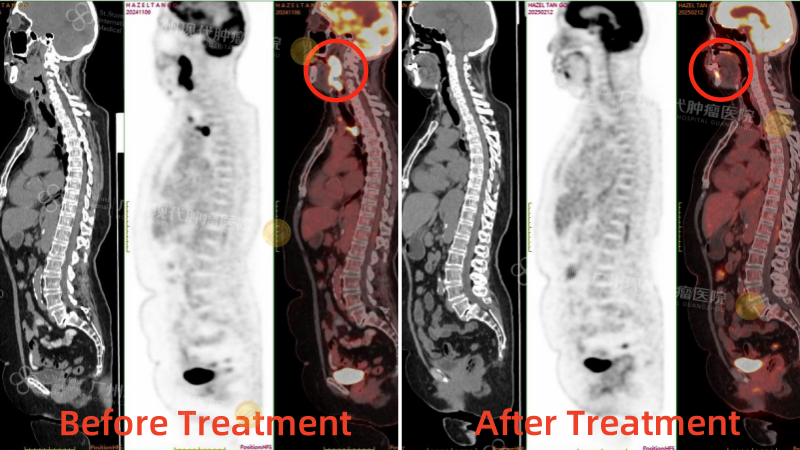

После четырёх сеансов лечения моя тётя прошла повторное ПЭТ-КТ, которое показало значительное уменьшение опухоли ротоглотки. Первоначальная опухоль размером 4,3 x 3,9 см уменьшилась до 1,7 x 1,8 см, а часть опухоли даже исчезла. Значение SUV-метаболизма снизилось с 26,4 до 7,2, что значительно снизило активность опухоли. В других метастатических зонах также наблюдалось значительное улучшение. Эти результаты были невероятно обнадеживающими. Выздоровление тёти шло на поправку. У неё не только улучшился цвет лица, вернулся аппетит, она начала набирать вес, но и стала более жизнерадостной и разговорчивой.

Сравнение результатов ПЭТКТ до и после лечения